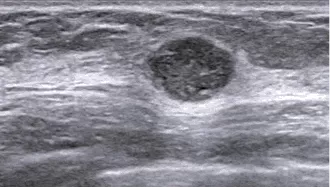

Hình 1. Một ví dụ về hình ảnh siêu âm

(Nguồn: https://www.nature.com/articles/s41598-018-27222-6)

Hình dạng và cường độ của các tín hiệu hồi âm phụ thuộc vào độ đậm đặc của mô. Ví dụ, hầu hết sóng âm sẽ đi xuyên qua một nang chứa dịch và chỉ tạo ra rất ít hoặc tín hiệu hồi âm rất yếu, khiến nang này hiển thị màu đen trên màn hình. Ngược lại, sóng âm sẽ bị khối u đặc dội lại, tạo nên một kiểu hồi âm mà máy tính sẽ hiển thị dưới dạng hình ảnh sáng hơn.